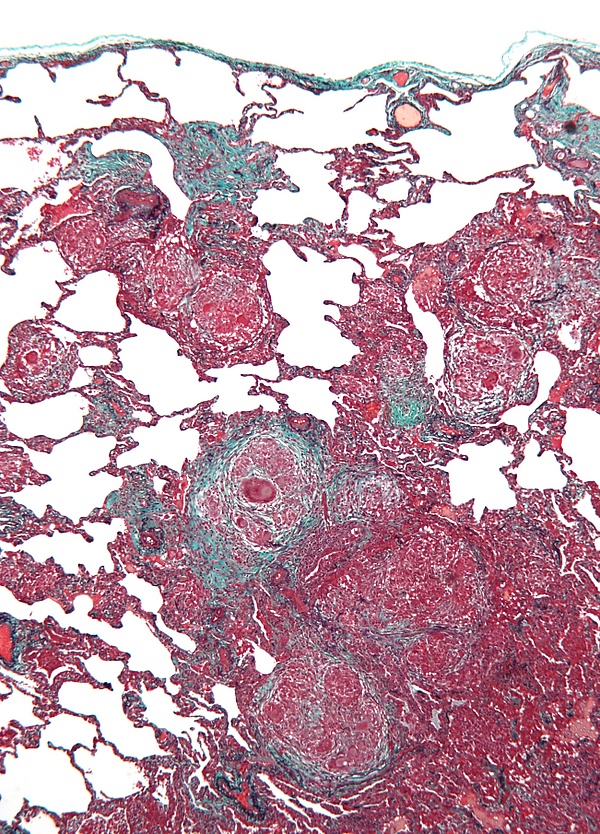

Биопсия легкого позволяет уточнить диагноз в неясных случаях. Сначала проводят трансбронхиальную биопсию. Если она недостаточно информативна и диагноз остается неясным, показана открытая биопсия легкого. Гистологическая картина экзогенного аллергического альвеолита весьма характерна, хотя не патогномонична. Если биопсия проведена при острой форме заболевания, типичны интерстициальная и альвеолярная инфильтрация из плазматических клеток, лимфоцитов, эозинофилов и нейтрофилов, иногда в сочетании с гранулемами. Васкулит при экзогенном аллергическом альвеолите не развивается[8].